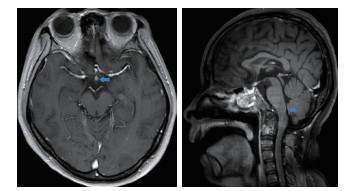

对患者再次进行神经系统查体:患者神志清楚,查体配合,智能可。双眼闭合力弱,双侧水平注视时可见持续粗大水平眼震,咬合力弱,转头耸肩力量可,四肢肌力5-级,膈肌与肋间肌肌力正常,痛觉大致正常,双上肢腱反射+++,双髌阵挛阳性,跟腱反射+++,双侧病理征阳性,颈以下皮肤划痕征阳性。因双眼闭合力弱,水平眼震,发病时呕吐,患者病变定位于脑桥背侧及小脑联系纤维;吞咽困难、球麻痹、呼吸障碍,定位于延髓背侧;前胸后背疼痛、皮肤划痕征阳性,定位于高颈段。2018年5月24日行脑脊液穿刺检查,脑脊液呈无色透明状,压力120 cmH2O。脑脊液常规:潘氏反应阴性,细胞总数3×106/L,白细胞2×106/L,红细胞1×106/L;脑脊液生化:蛋白0.4 g/L,氯离子124 mmol/L,糖5.58 mmol/L;脑脊液外送检验结果以及住院期间其他外送检验结果见表 4。其中脑脊液抗水通道蛋白抗体(AQP4-IgG)3+。2018年5月31日患者头颅磁共振检查提示:视神经分叉部、颈髓-延髓移行区异常对比增强(图 3)。结合患者临床表现,脑脊液AQP4-IgG阳性,以及头颅磁共振结果,患者最终诊断视神经脊髓炎谱系疾病。该患者后续经过激素维持治疗及康复锻炼于2018年6月5日拔除气管插管,患者吞咽功能逐渐恢复于2018年7月10日拔除胃管,2018年9月20日患者病情进一步好转出院。出院后3个月随访,患者一般情况好,生活自理,未遗留视力及其他器官功能障碍。